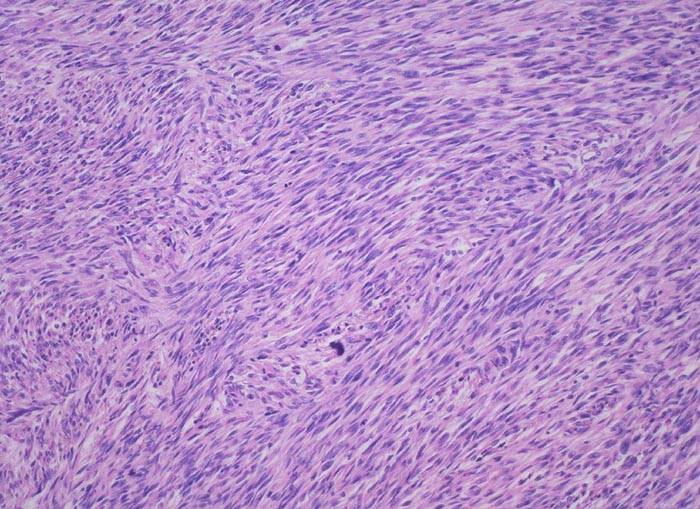

PathoPic ID 4435 - uterines Leiomyosarkom

uterines Leiomyosarkom

maligner Tumor

Uterus

Genitalorgane, weiblich

Zu breiten Bündeln angeordnete Tumorzellen mit geringen Kernatypien.

Mitosen.

Die Patientin sucht wegen postmenopausaler Blutung den Gynäkologen auf. Dieser palpiert einen stark vergrösserten Uterus.

Histologie

100

64